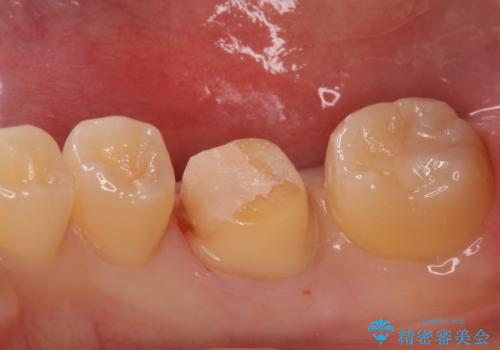

- 過去に退院で治療した詰め物が欠けたことにより来院。

古いプラスチックの樹脂、虫歯を全て取り除き

ジルコニアクラウンにて治療しました。

プラスチックの樹脂(CR)の治療は保険適応で白くて一日で

治療が終わるため安価であり、患者様の負担が少ない治療ですが

プラスチック樹脂は経年劣化して茶色くなります。

また耐久性もジルコニアクラウンに比べて低く、割れてしまうことがあります。